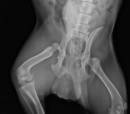

I decided we all needed some good news, and Pluto is the perfect candidate to share all the good coming his way.  Our sweet pup could barely walk when he first arrived.  His hip had been displaced for so long that it had changed his entire gait.  He had a giddy-up in his step that you would typically find in a very old dog.  His ears hurt all the time from infection, and he could barely hear what you were saying.

He now has a very cool walk with his personality and can hear everything you say, even if he ignores it.   Pluto has not had one problem with any of his procedures.  He breezed through each with the careless, lazy attitude of what's the big deal.